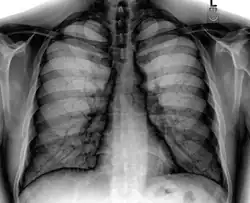

A normal posteroanterior (PA) chest radiograph of someone without any signs of injury. Dx and Sin stand for "right" and "left" respectively.

A chest radiograph, chest X-ray (CXR), or chest film is a projection radiograph of the chest used to diagnose conditions affecting the chest, its contents, and nearby structures. Chest radiographs are the most common film taken in medicine.